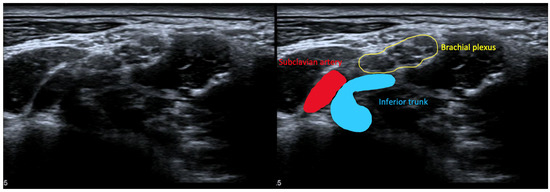

6.3.4. High-Resolution Ultrasound for NTOS

- Dollinger, P.; Böhm, J.; Arányi, Z. Combined nerve and vascular ultrasound in thoracic outlet syndrome: A sensitive method in identifying the site of neurovascular compression. PLoS ONE 2022, 17, e0268842. [Google Scholar] [CrossRef] [PubMed]

- Pesser, N.; Teijink, J.A.W.; Vervaart, K.; Goeteyn, J.; Gons, R.A.R.; van Sambeek, M.R.H.M.; van Nuenen, B.F.L. Value of Ultrasound in the Diagnosis of Neurogenic Thoracic Outlet Syndrome. Eur. J. Vasc. Endovasc. Surg. 2020, 59, 852–853. [Google Scholar] [CrossRef] [PubMed]